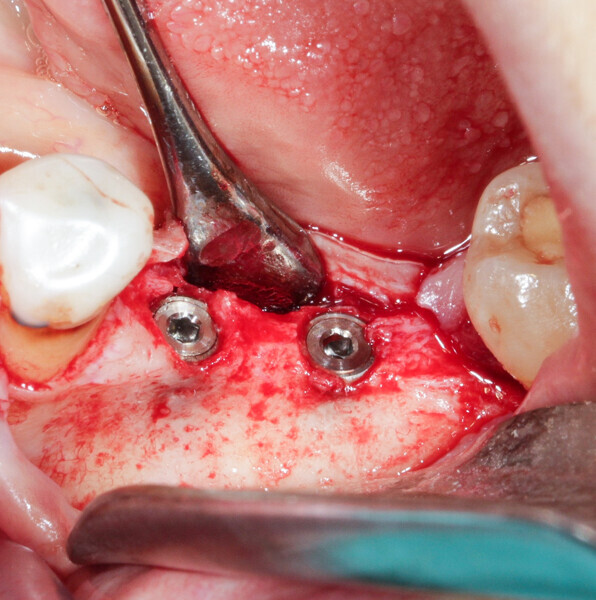

We had three alternative courses of action: a bone block graft from the mandibular ramus,2 a segmental osteotomy4 or a radicular graft, knowing that tooth #46 could not be saved. We chose the third option because it allowed for simultaneous implant placement and bone reconstruction. A large flap was elevated to assess the gap in the bone and in anticipation of closing the flap on an augmented ridge. Two implants were placed as normal despite the low residual bone thickness in the vestibular area of the planned positions for the implants (Fig. 5). The roots of tooth #46 were extracted atraumatically (root separation, use of piezo-surgery, etc.) and were then prepared as described. The roots were shaped to fit the defect and fixated at the insertion site using osteosynthesis screws (Fig. 6).3 The flap was mobilised and stretched to achieve edge-to-edge closure without tension, and a 4/0 rapidly resorbed braided thread was used for the sutures (Fig. 7). Four months after the bone augmentation and implant placement, healing abutments were connected to the implants and the osteosynthesis screws removed (Figs. 8 & 9). During the operation, time was taken to perform a visual check that ankylosis of the radicular grafts had been successful and that these were sound. Finally, a CBCT assessment was performed. The prosthesis was fitted by our colleague a few weeks later, once the soft tissue had healed.

Case 1

A 36-year-old patient with teeth #36 and 37 missing and transverse bone insufficiency in the existing gap was treated. It would have been possible to place implants, but this would have left only a thin layer of vestibular bone at the neck of the implants. There was a serious risk of dehiscence, which can compromise the survival of the implant in the arch (Fig. 4).